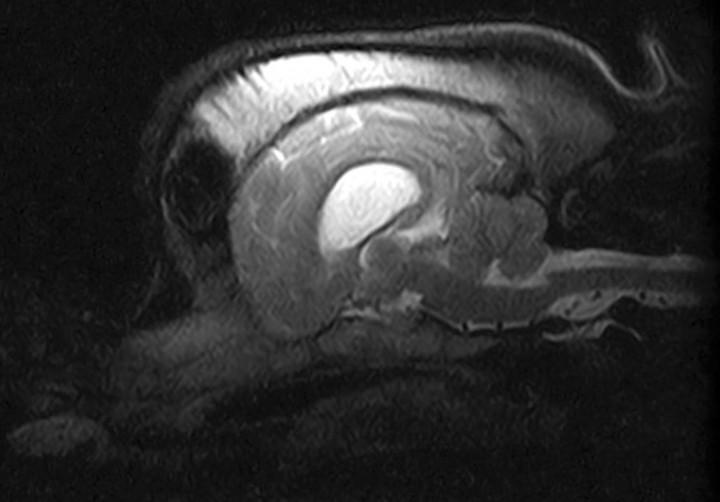

Transcurridos 6 meses se realizó una segunda TC en la que la lesión ósea se mantenía en dimensiones similares, pero con una disminución considerable de la atenuación ósea en comparación con la primera (Fig. 2B). Esta vez se procedió a realizar también una resonancia magnética (RM) para comprobar que la lesión no afectase a otras estructuras (Fig. 3). Se observó una dismorfia del hueso frontal derecho que deformaba el cráneo en ese lado, sin que existiera un crecimiento óseo hacia el interior de la cavidad craneal. El seno frontal derecho presentaba mayor tamaño, pero estaba normalmente neumatizado. No se observaron alteraciones en los demás huesos que configuran la bóveda craneal ni la base del cráneo. Respecto al parénquima cerebral, cerebeloso y tronco cerebral, no se observaron alteraciones estructurales ni de la señal valorables en las distintas secuencias realizadas.

Figura 3

Imagen de Resonancia Magnética, plano sagital en T2. No se observan lesiones en estructuras adyacentes.